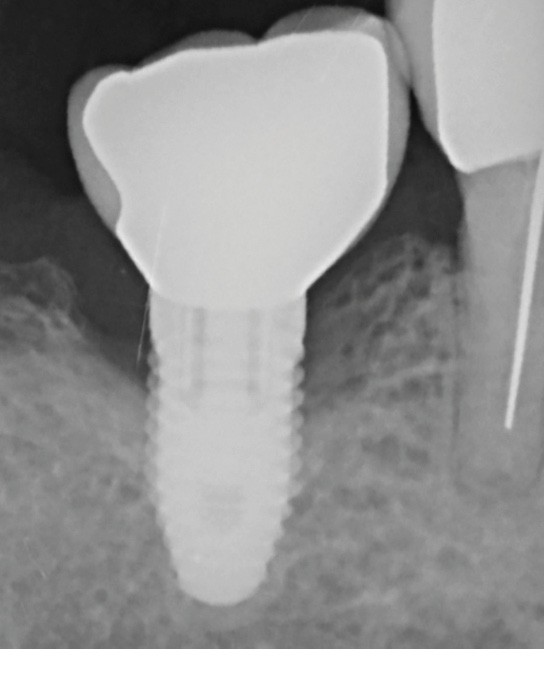

La patiente est restée 4 semaines sans couronne. Après l’intervention chirurgicale, elle a entamé un programme de soins péri-implantaires et parodontaux, avec des visites de rappel tous les 4 mois.

Dans les cas de traitement de péri-implantite, un suivi d’un an est considéré comme un suivi court. Néanmoins, le cas présent est stable après un an et ne présente aucun signe de récidive. Des contrôles supplémentaires sont nécessaires.